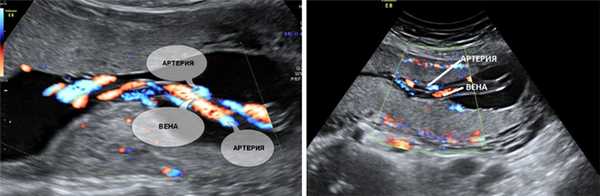

5. Единственная артерия пуповины.

Нормальная пуповина состоит из трех сосудов - две артерии и одна вена. Иногда вместо двух артерий в пуповине формируется только одна артерия и одна вена, таким образом, в пуповине определяется всего два сосуда. Данное состояние считается пороком развития пуповины, однако этот порок не оказывает никакого влияния на послеродовое состояние ребенка и его дальнейшее развитие.

Почему у плода может определяться единственная артерия пуповины?

Иногда единственная артерия пуповины выявляется у абсолютно нормальных плодов; после рождения ребенка данный факт не оказывает никакого влияния на его дальнейшее развитие. Иногда единственная артерия пуповины сочетается с пороками сердечно-сосудистой системы плода, поэтому при выявлении единственной артерии пуповины проводится детальный осмотр анатомии плода и, в частности, сердечно-сосудистой системы. При отсутствии других пороков развития единственная артерия пуповины в состоянии обеспечить адекватный кровоток плода. Несколько чаще единственная артерия пуповины выявляется у плодов с синдромом Дауна и другими хромосомными болезнями. Однако этот маркер относится к «малым» маркерам синдрома Дауна, поэтому выявление только единственной артерии пуповины не повышает риск наличия синдрома Дауна и не является показанием к проведению других диагностических процедур. Единственная артерия пуповины иногда приводит к возникновению задержки внутриутробного развития плода. В связи с этим при обнаружении единственной артерии пуповины рекомендуется дополнительное УЗИ в 26-28 недель беременности, и плановое в 32-34 недели. Если отставание размеров плода от срока беременности или нарушение кровотока в сосудах плода и матки не выявлено, то диагноз задержки развития плода исключен.

Что делать при выявлении единственной артерии пуповины у плода?

Выявление только единственной артерии пуповины не повышает риск наличия синдрома Дауна и не является показанием к консультации генетика и проведению других диагностических процедур. Необходимо контрольное УЗИ в 26-28 и 32 недели беременности для оценки темпов роста плода и оценки его функционального состояния.